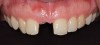

The patient was brought back weekly for 4 weeks for postoperative follow-up. Healing was satisfactory (Figure 18). Four months after implant placement, the final restoration, a porcelain-fused-to-metal screw-retained crown, was inserted at site No. 8 (Figure 19).

Fig 19. Final screw-retained crown on implant at site No. 8.

Figure 19